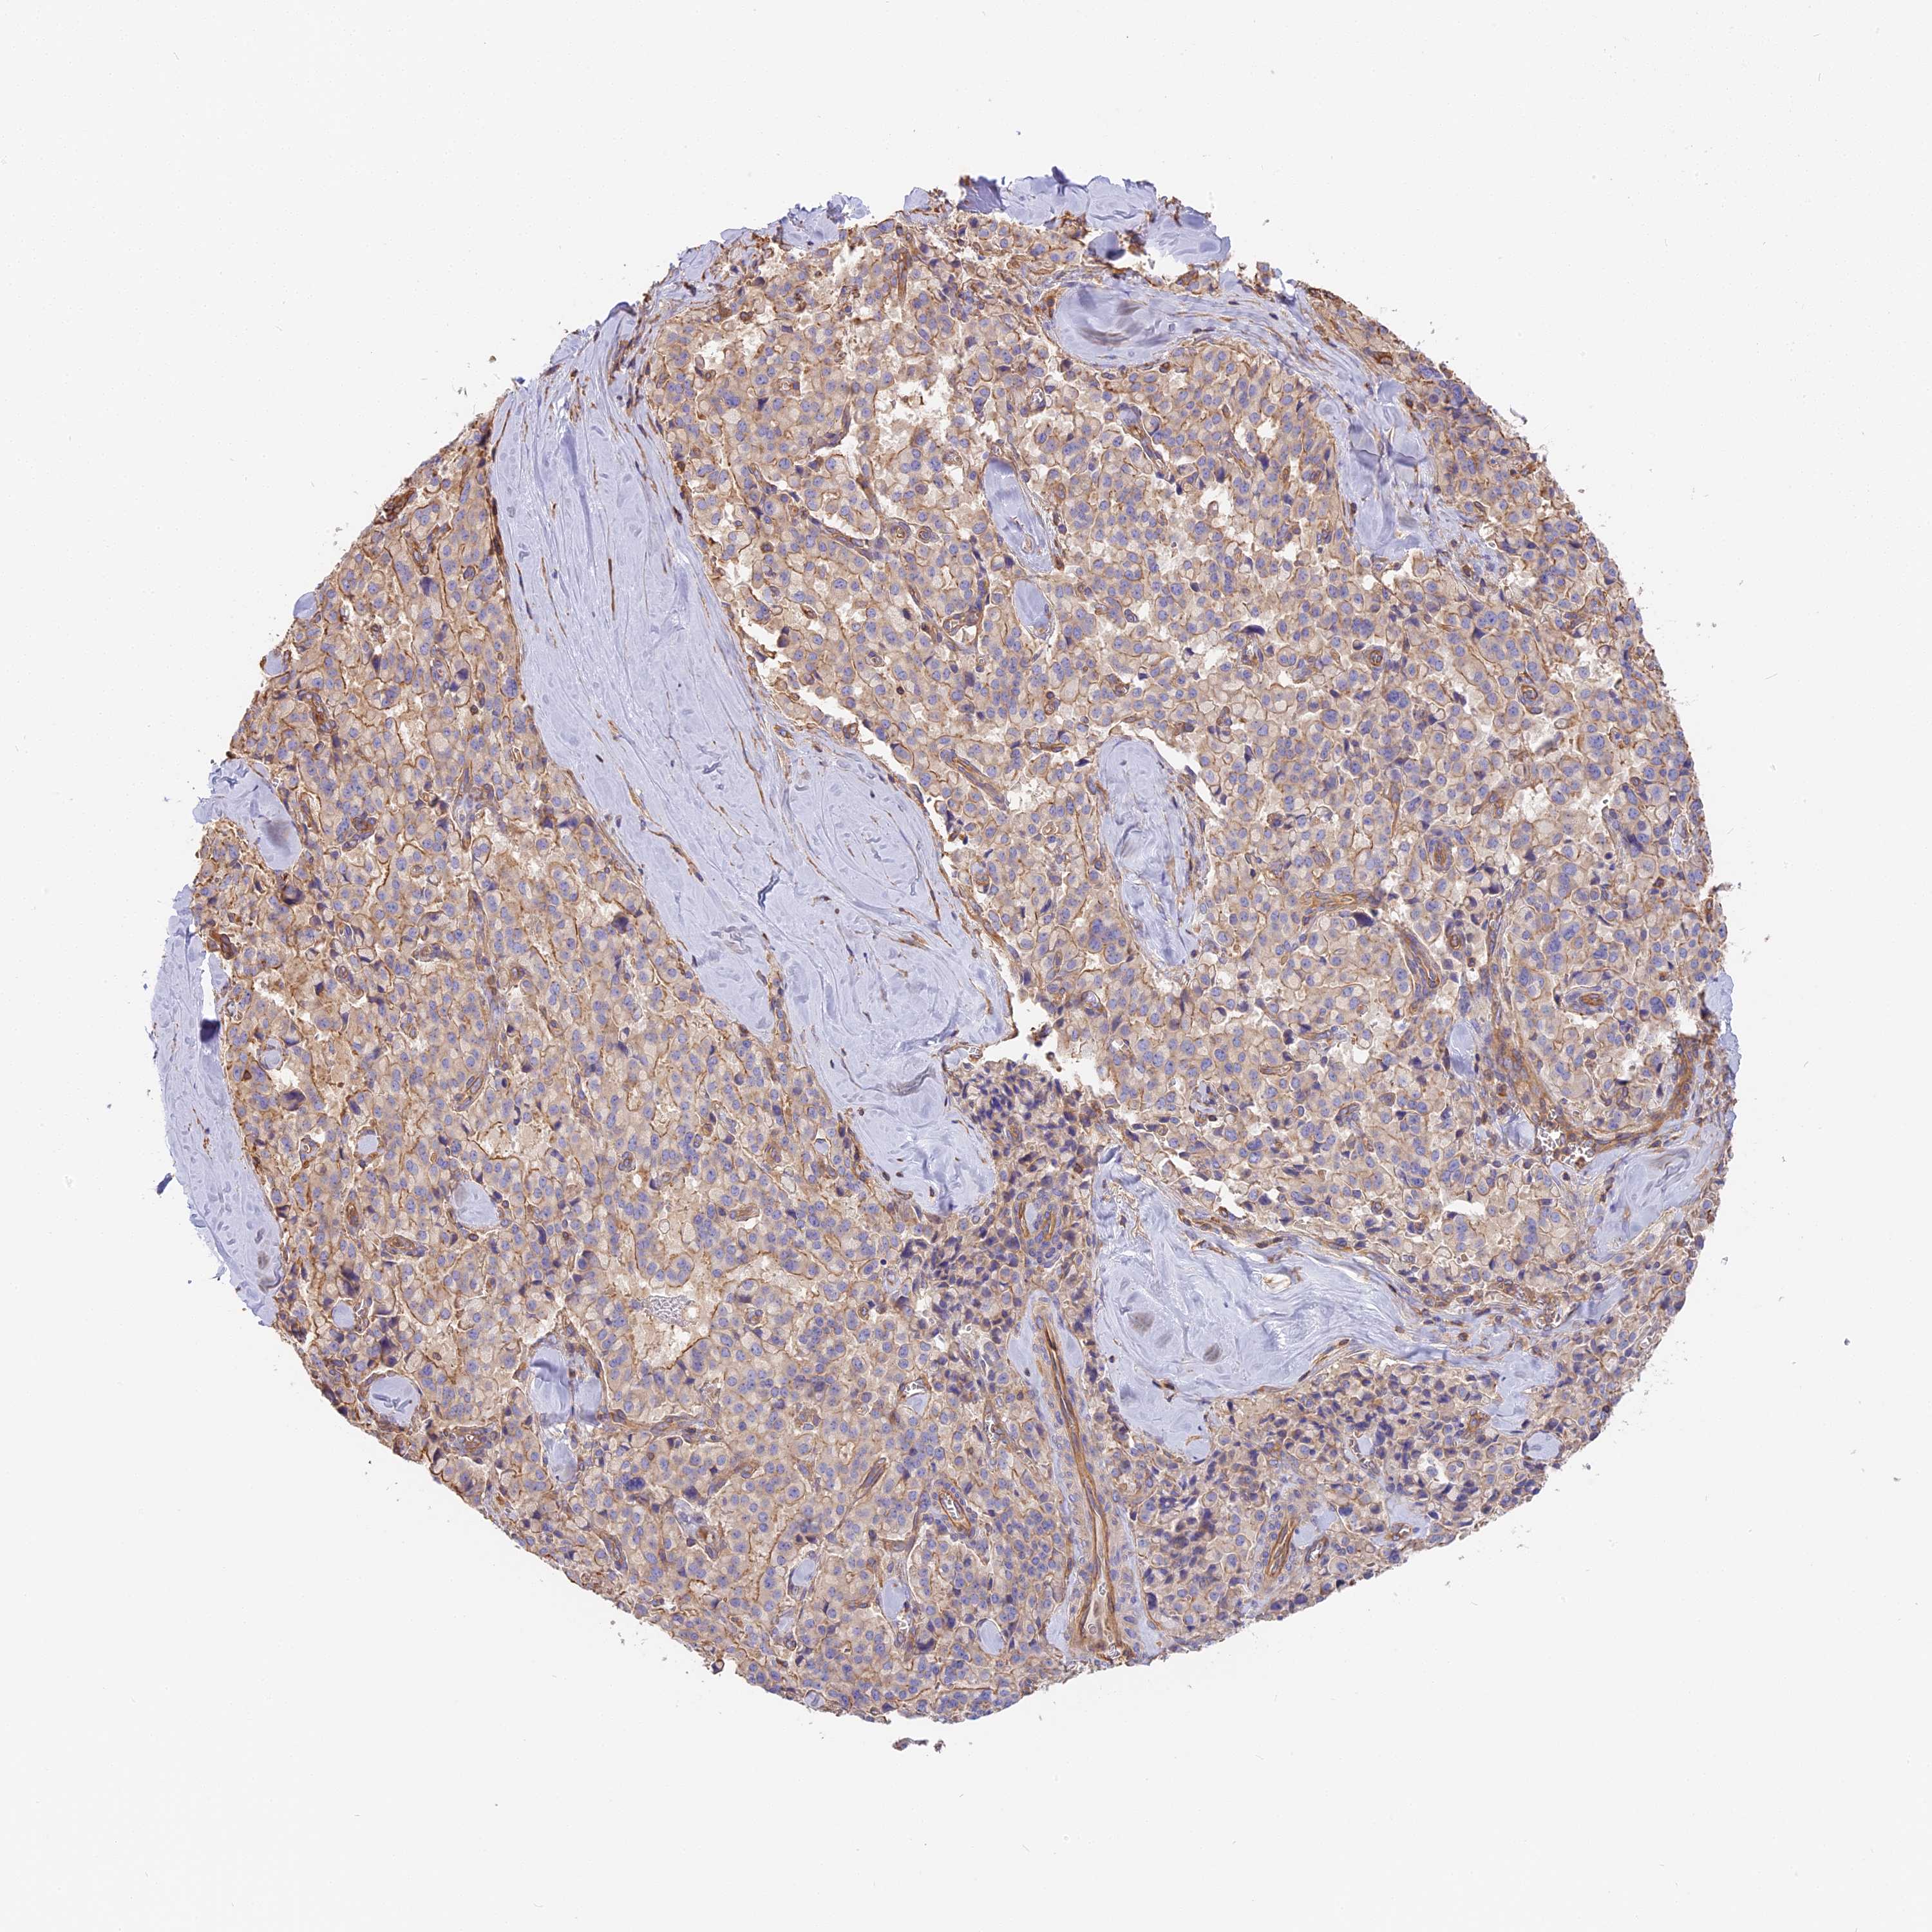

PANCREATIC CANCER - Protein expressioni

A mouse-over function shows sample information and annotation data. Click on an image to view it in a full screen mode. Samples can be filtered based on level of antibody staining by selecting one or several of the following categories: high, medium, low and not detected. The assay and annotation is described here.

Note that samples used for immunohistochemistry by the Human Protein Atlas do not correspond to samples in the TCGA dataset.

Antibody stainingi

Antibody staining in the annotated cell types in the current human tissue is reported as not detected, low, medium, or high, based on conventional immunohistochemistry profiling in selected tissues. This score is based on the combination of the staining intensity and fraction of stained cells.

Each image is clickable and will lead to virtual microscopy that enables deeper exploration of all samples and also displays staining intensity scores, fraction scores and subcellular localization as well as patient and tissue information for each sample.

Antibody HPA040701

Staining

High

Medium

Low

Not detected

Intensity

Strong

Moderate

Weak

Negative

Quantity

>75%

75%-25%

<25%

None

Location

Nuclear

Cytoplasmic/membranous

Cytoplasmic/membranous,nuclear

Adenocarcinoma, NOS